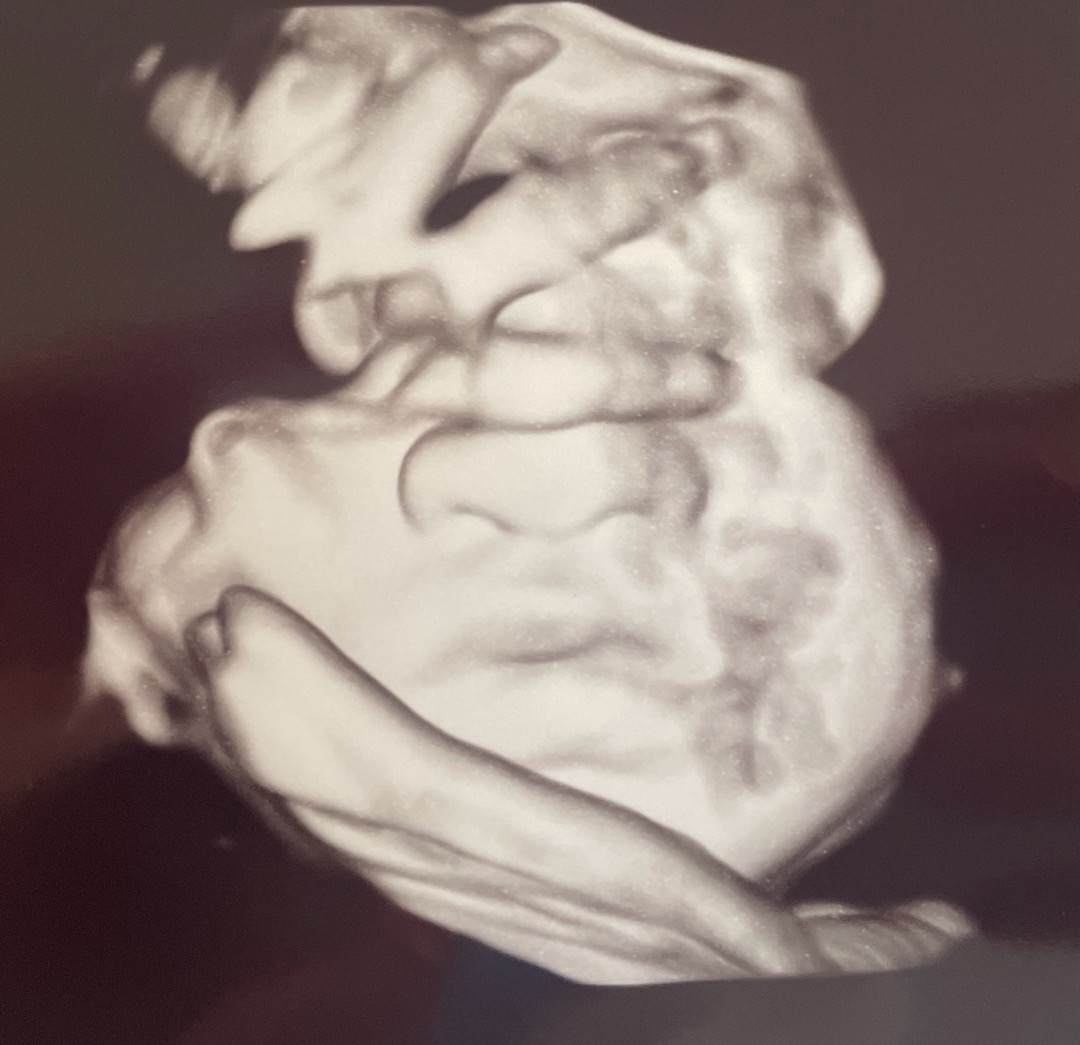

30주 초음파까지는 예뻤는데.. 그 이후로는 애가 너무 넙대대하게 변해서;;; 양수때문에 불은거라 생각하고있습니다;;;

코가..찌부인가요?ㅋㅋ

미국은 워낙 촘파를 안해줘서.. 첨이자 마지막 3D 사진 찍었는데 코랑 입이 생각보다 ㅋㅋㅋㅋ 찌부가 되어있어서 …. 35주인데 지금쯤 다른분들 아기들두 이렇게 생겼나요.??ㅋㅋㅋ 게다가 손으로 얼굴을 계속 가리고 있어서 정확히 보지도 못했네요🥹🥹😭😭

자궁벽이나 손으로 만지고 있을때 찍으면 코가 눌리더라구용ㅎㅎㅎ

제 친구 애기도 초음파에서는 코가 찌부돼서 넙대대해보였는데 태어난지 3주 된 사진 보니까 오똑해요 ㅋㅋㅋ